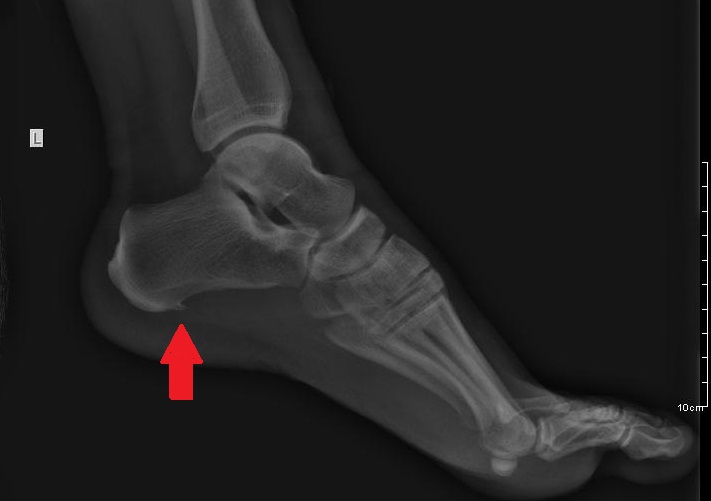

DIJAGNOSTIKA SE SPROVODI KLINIČKIM PREGLEDOM I RADIOLOŠKIM PREGLEDOM.

SAM PETNI TRN SE VIDI NA RENGENSKOM SNIMKU KAO NAKUPINA KALCIJUMA NA PRIPOJU PLANTARNE FASCIJE ZA PETNU KOST.